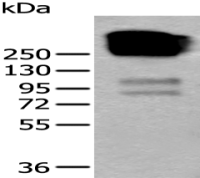

Positive control: Human colorectal cancer

Recommended dilution: 30-150

The image on the left is immunohistochemistry of paraffin-embedded Human lung cancer tissue using ml224923(BCAS3 Antibody) at dilution 1/35, on the right is treated with fusion protein. (Original magnification: ×200) The image on the left is immunohistochemistry of paraffin-embedded Human colorectal cancer tissue using ml224923(BCAS3 Antibody) at dilution 1/35, on the right is treated with fusion protein. (Original magnification: ×200)